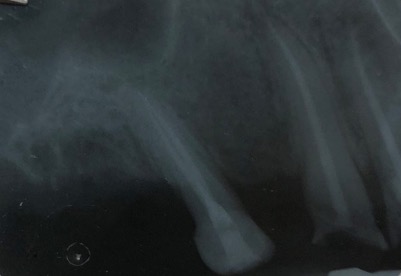

Capita spesso di incontrare denti già devitalizzati in maniera impropria che necessitano, seppur asintomatici, di essere ritrattati per evitare che i granulomi infetti visibili radiograficamente si evolvano riassorbendo tutto l’osso sottostante.